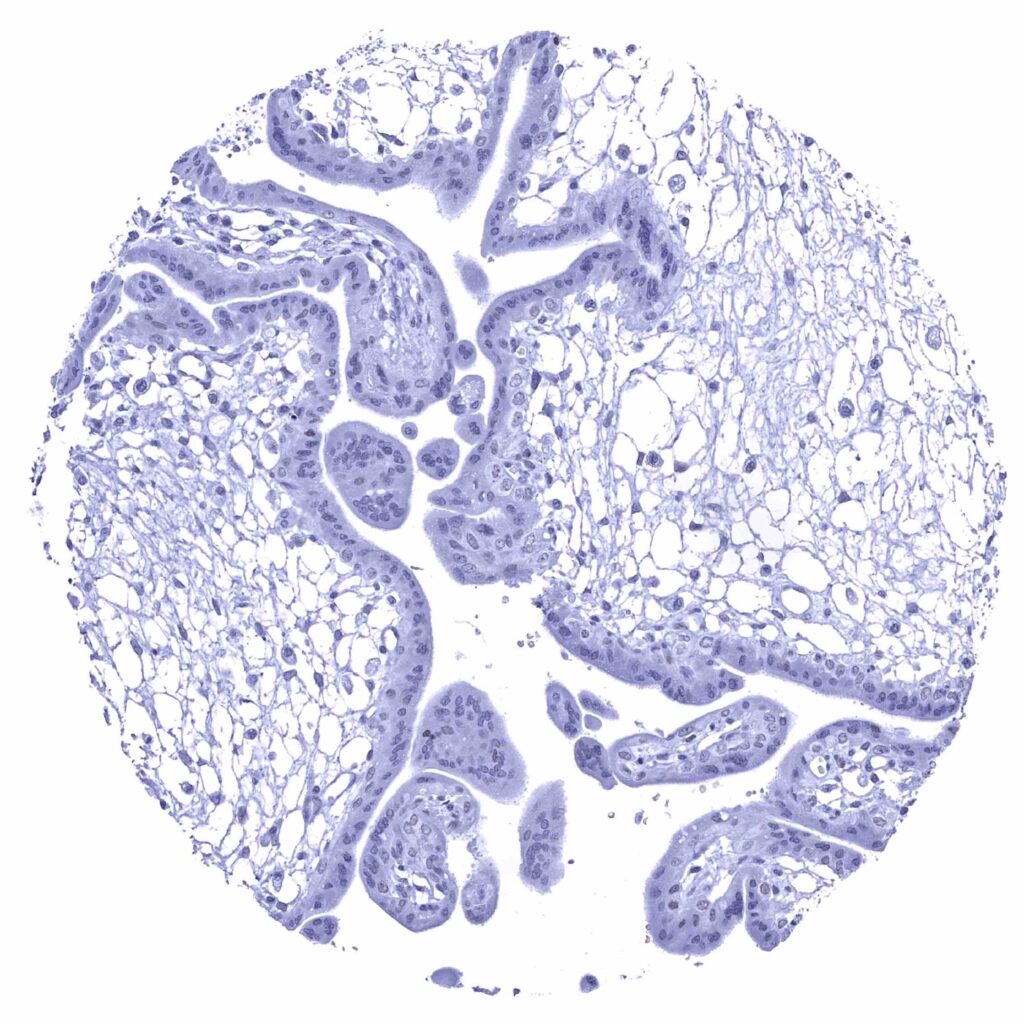

Kidney, cortex – Faint nuclear p53 staining of a small fraction of tubular cells (p53 immunohistochemistry).